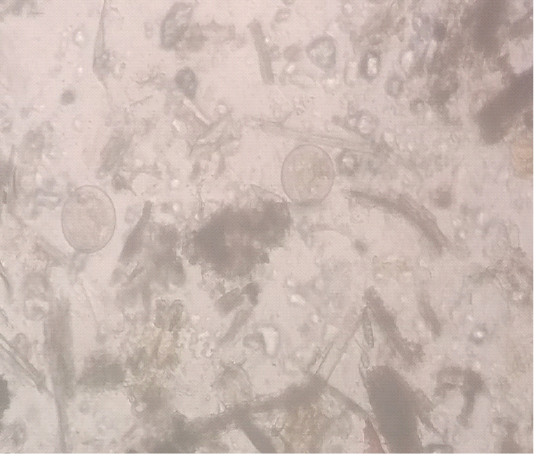

Figure 1

Figure Balantidium coli trophozoites in Fecal Sample of Buffalo